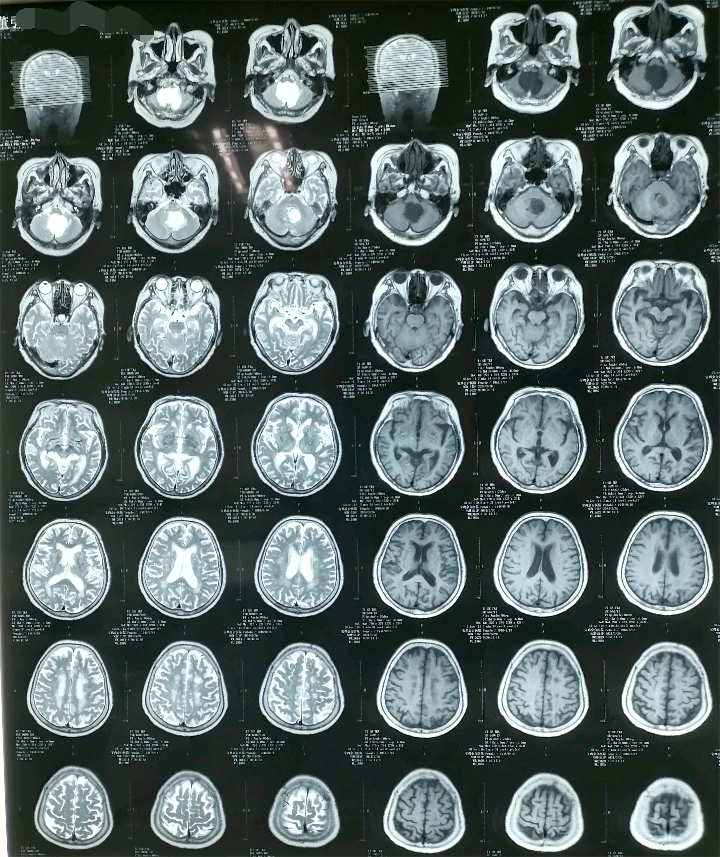

初步诊断:枕大孔区占位性病变 血管母细胞瘤

术前资料